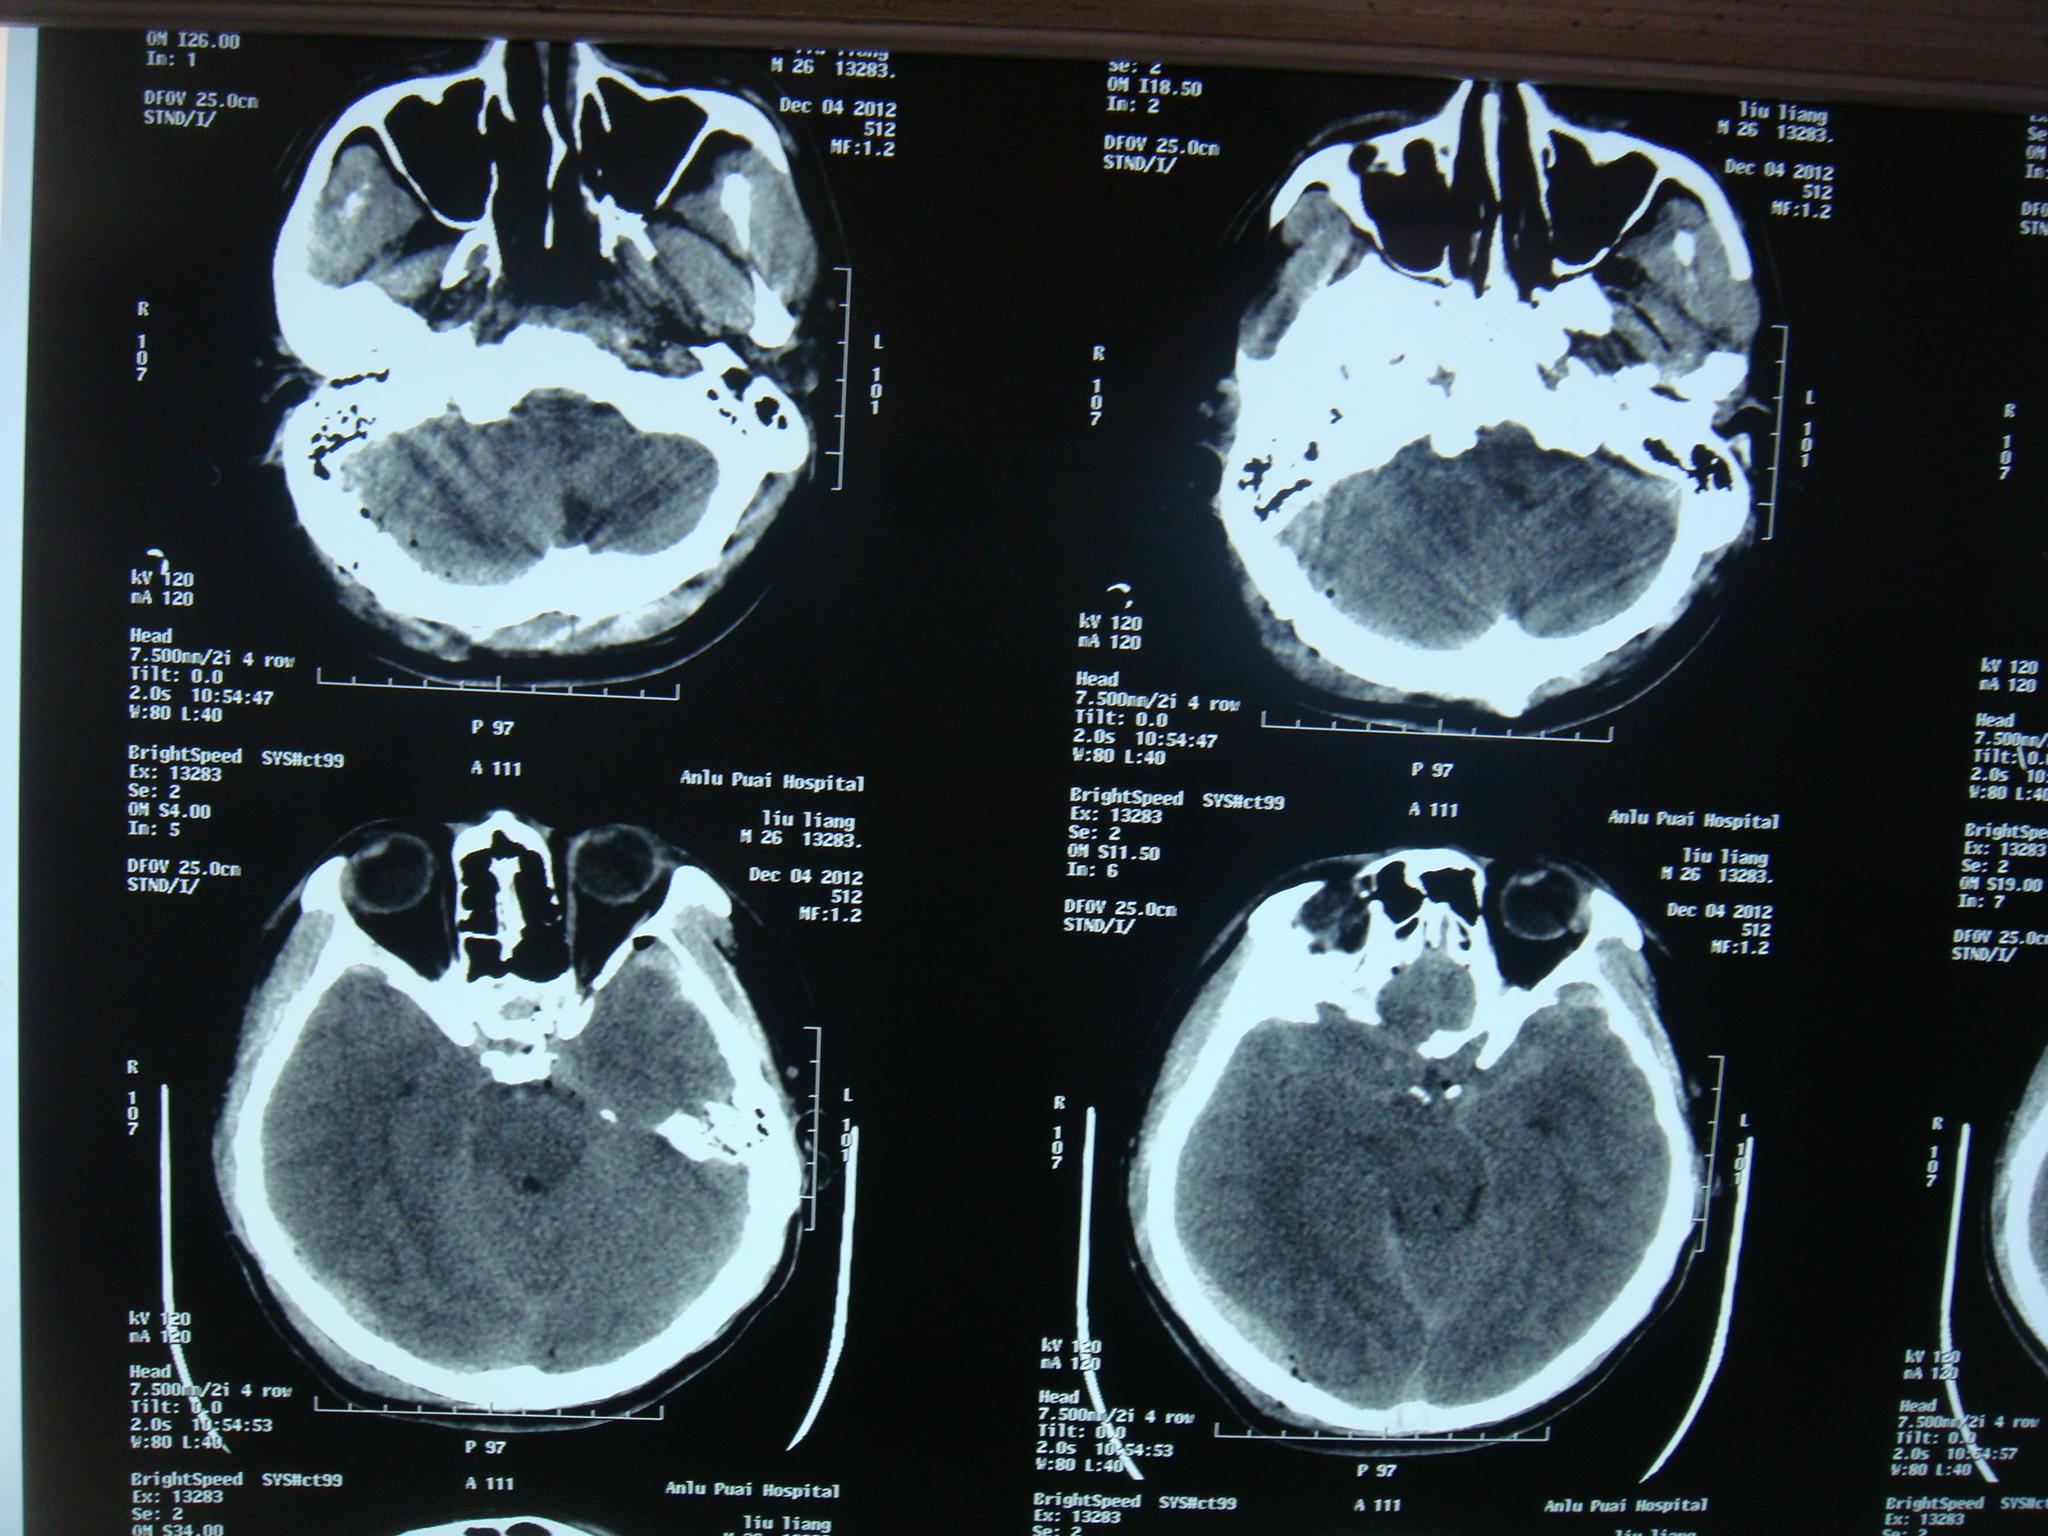

2.审查某市医院病历:某市医院某号住院病历记载:刘某于某年12月4日晨5时许因头部外伤半小时入院。入院检查:神清,嗜睡,自诉头痛,并向护士告知家庭住址及电话号码。双瞳孔等大等园,对光反射灵敏。12月4日5时54分头颅CT扫描提示: 右枕骨骨折,右枕部少量硬膜外血肿,左颞部硬膜下小血肿,蛛网膜下腔出血;给予脱水、止血、激素等药物治疗。入院50分钟后,意识障碍逐渐加深至昏迷。当日12时50分行第二次头颅CT复查。报告:右顶枕部大片状高密度影,同侧脑室、脑池受压、脑沟消失,中线结构左移,提示右枕顶部硬膜外血肿明显扩大伴脑疝形成,右顶枕骨骨折伴外伤性气颅,蛛网膜下腔出血,脑肿胀。立即送手术室准备开颅手术。麻醉前呼吸心跳聚停,紧急作心肺复苏,同时开颅血肿清除,去骨瓣减压。但呼吸循环功能仍未能恢复,当日14时宣布临床死亡。死亡诊断:右颞枕顶部硬膜外血肿,脑疝形成。

某年12月4日5:54分刘某入院当时CT显示